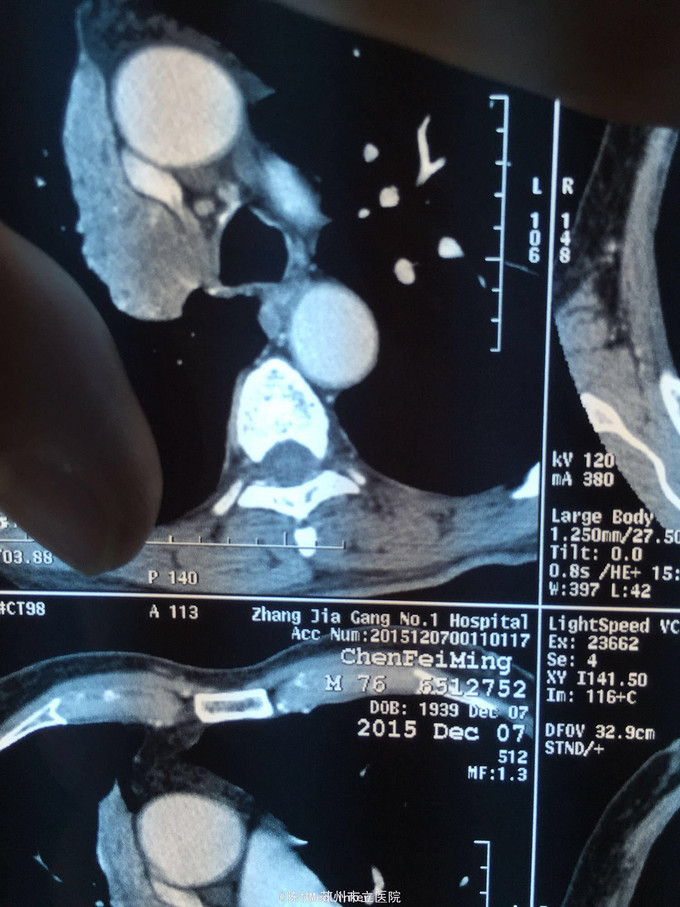

主诉:体检发现右上肺不张半月 77岁男,半月前体检发现右上肺不张,无不适。无消瘦,无咳血,无干咳。去年4月右上肺炎,抗生素治愈,当时CT未见肺肿块。入院支气管镜发现右上支气管开口组织增厚闭塞,开口近侧有隆起约3x3平方毫米,取活检5块病理示中度非典型增生。CT提示在右侧主支气管外侧有30x30平方毫米块影,压迫右上支气管开口处。三大常规和生化检查正常,肿瘤指标正常,TAP正常。

右侧中央型肺癌 重做支气管镜,精于定位找到病症组织,获得病理诊断来指导治疗。 胸外科医生不建议手术,理由是肿瘤位置靠近主支气管和气管,袖状切除不一定看干净。 请问正确的诊断,和比较合理的治疗方法是什么?求助大家思考评论